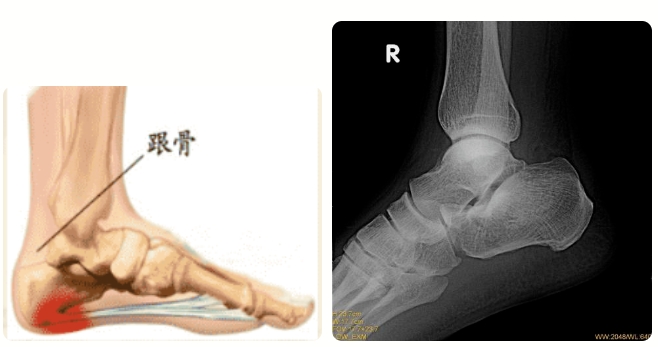

跟骨骨折后该怎么护理呢?九州娱乐app 手足外科教你几个小妙招